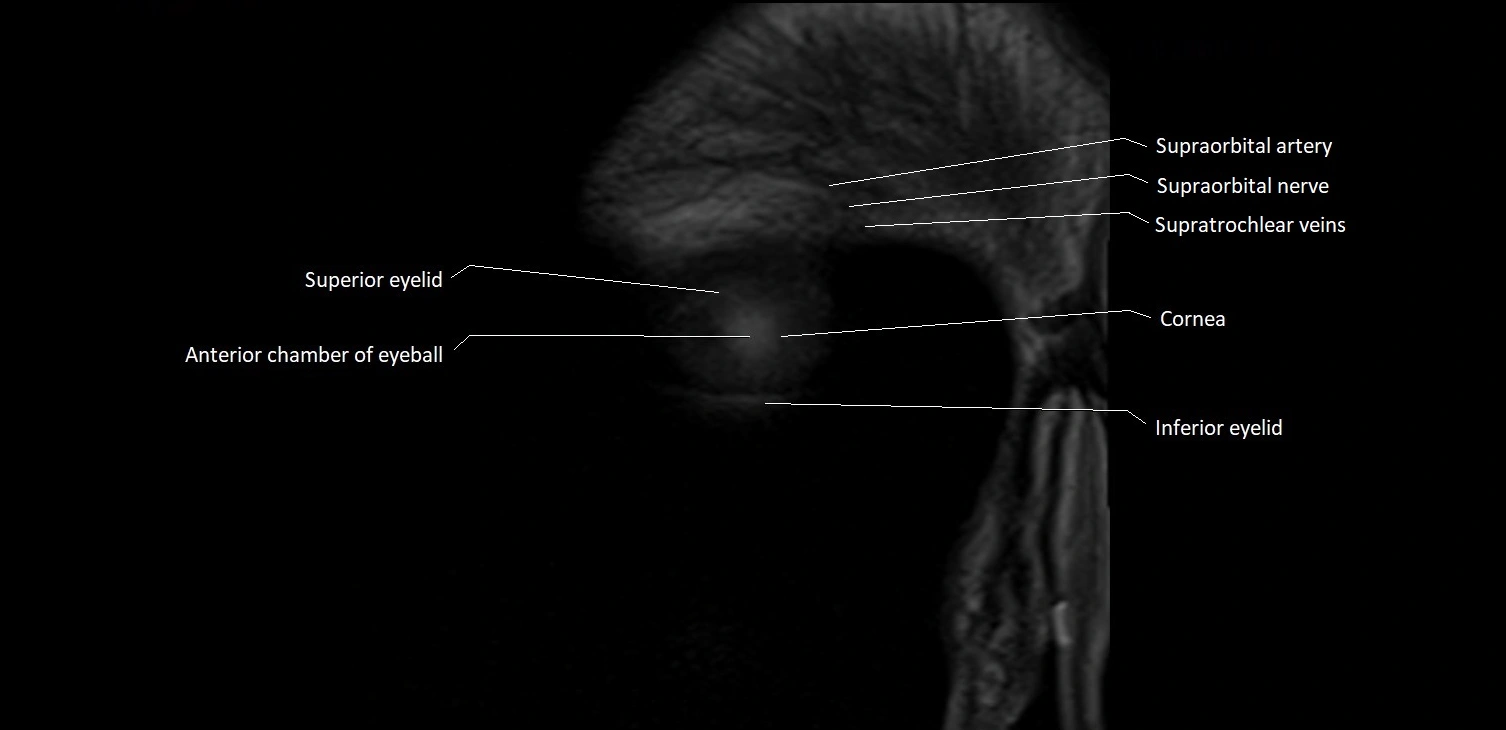

- Anterior chamber of eyeball

- Cornea

- Inferior eyelid

- Superior eyelid

- Supraorbital artery

- Supraorbital nerve

- Supratrochlear vein